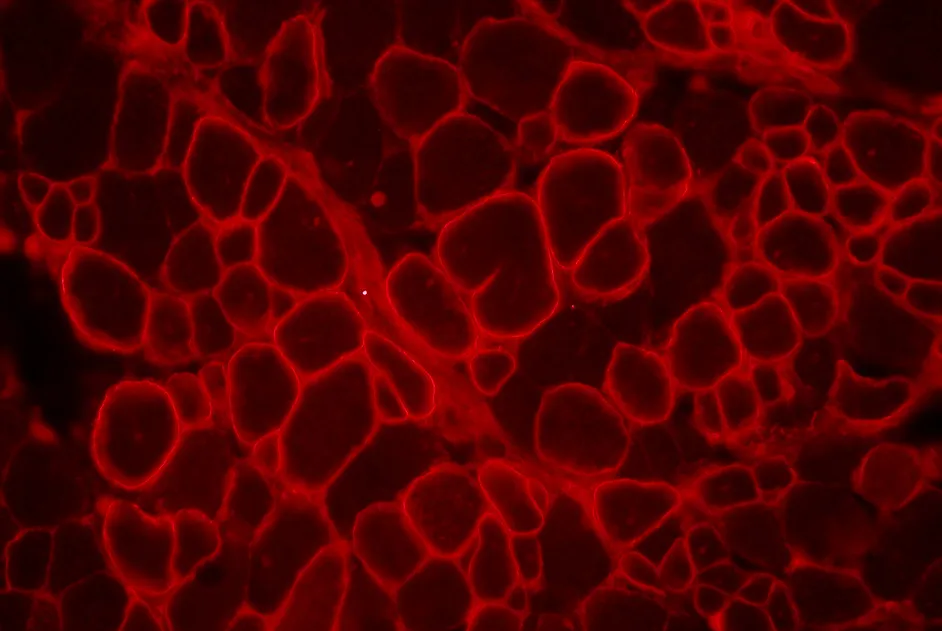

Une équipe américano-coréenne rapporte dans un article publié en janvier 2013 les effets de l’administration d’un AAV9 transportant une micro-dystrophine dans un muscle de la patte antérieure de chiens dystrophiques et de chiens contrôles. Chez les chiens dystrophiques, les chercheurs ont observé une expression nette de la microdystrophine, une restauration du complexe de glycoprotéines associées à la dystrophine ainsi qu’une réduction des lésions tissulaires dans les muscles des chiens traités. Ces résultats apportent la preuve de concept de l’efficacité d’une thérapie génique avec le gène de microdystrophine dans un modèle de mammifère de grande taille.